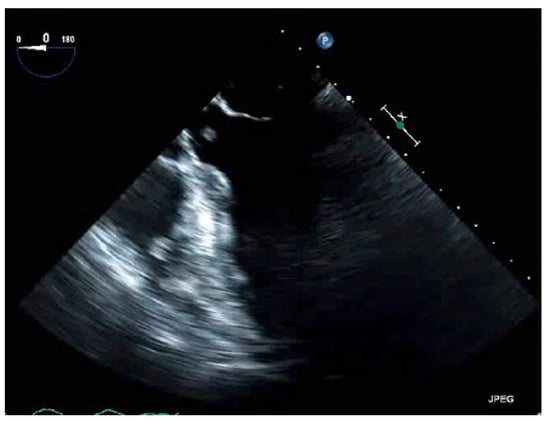

Thrombus in Transit

Case presentation